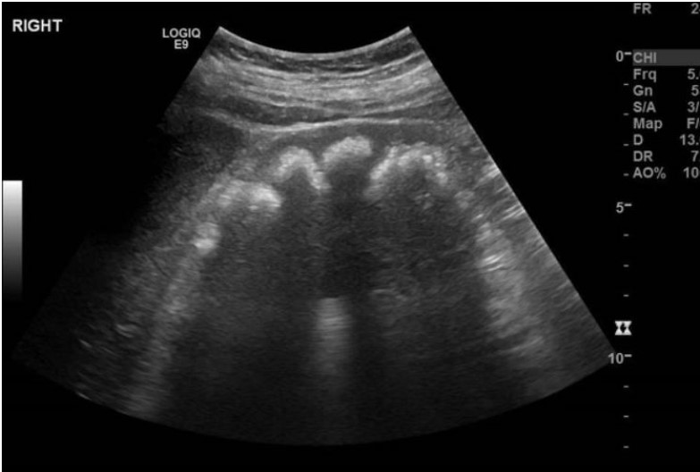

Um lactente de 8 meses é levado ao pediatra devido a irritabilidade, baixo ganho de peso e episódios recorrentes de vômitos nos últimos meses. Ao exame físico, apresenta-se emagrecido, sem sinais de desidratação, mas com atraso no crescimento. A investigação laboratorial revela acidose metabólica com ânion gap normal. pH arterial de 7,22; PCO2 de 28 mmHg, bicarbonato sérico de 12 mEq/L, sódio sérico de 138 mEq/L, cloro 116mEql/L e potássio sérico de 3,0 mEq/L. A avaliação urinária mostra um pH urinário de 6,5. Na investigação foi solicitado ultrassom renal:

Foto: Radiopaedia.org

Com base nesses achados, qual é o diagnóstico mais provável?